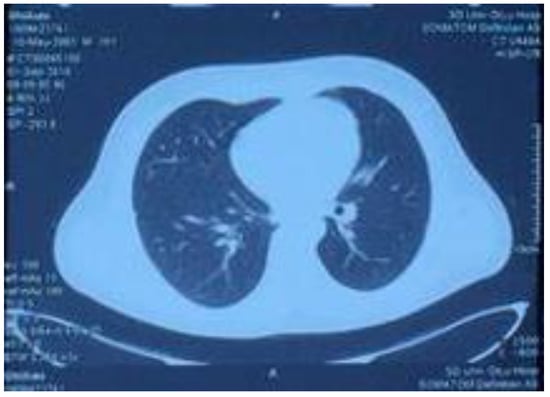

Lung CT performed on 15 August 2018, showing increased texture in both lungs, a patchy high-density shadow, unobstructed bronchi above the segment, and a patchy high-density shadow in the posterior segment of the lower lobe of the right lung.

On 15 August, the patient started coughing up yellow phlegm and had another fever spike; the highest reading reaching 38.9 °C. Sputum cultures and chest computed tomography examination were performed (Figure 4). The culture test results showed Pseudomonas aeruginosa and Escherichia coli growth. Consequently, the drug regimen was adjusted to imipenem 500 mg IV infusion Q 6 h according to the drug sensitivity test. The CT results showed increased texture of both lungs, a patchy high-density shadow, unobstructed bronchi above the segment, and a patchy high-density shadow of the lower and posterior segment of the right lung. Other laboratory tests revealed white blood cells, 7.12 × 109/L; neutrophils ratio, 67.10%; red blood cells, 3.92 × 1012/L; platelets, 248 × 109/L; serum myoglobin, 111.60 ng/mL; creatine kinase isoenzyme, 7.30 ng/mL; serum hypersensitive troponin I, 356.79 ng/L; and NT-probNP, 594.70 pg/mL. (Table 1) The patient’s symptoms significantly improved after weaning and adjusting antibiotics, and his body temperature gradually normalized. On 20 August, drug administration was stopped, and the patient’s condition improved; therefore, he was discharged. After discharge, he continued to take Jinshuibao and Qishen Yiqi pills orally.